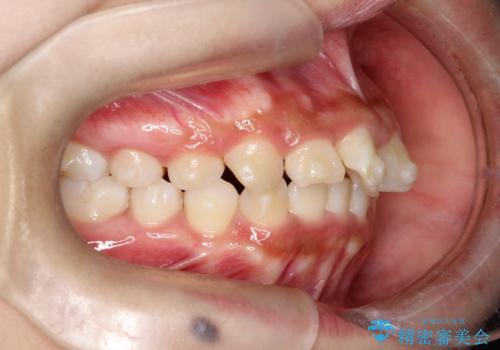

目立たない矯正で中等度の叢生を改善

- 歯のデコボコ(叢生)を気にされて来院されました。精密な検査の結果、中等度の叢生と診断。患者様のご希望に合わせ、透明で目立ちにくい**インビザライン(マウスピース矯正)**による治療計画を立案しました。歯を抜かずに、歯列弓(歯が並ぶアーチ)を少しずつ拡大することで、歯が並ぶスペースを確保し、叢生を改善することを目指します。

今回の矯正治療では、透明なマウスピース型の装置インビザラインを使用しました。この装置は目立ちにくく、取り外しが可能なため、食事や歯磨きも普段通りに行えます。治療は、緻密に計算された治療計画に基づき、段階的に作製されたマウスピースを交換していくことで、歯列弓全体を徐々に広げていきました。この歯列弓の拡大により、不足していたスペースを確保し、歯のデコボコを効果的に解消。抜歯することなく、整った美しい歯並びと良好な咬み合わせを獲得していただけました。